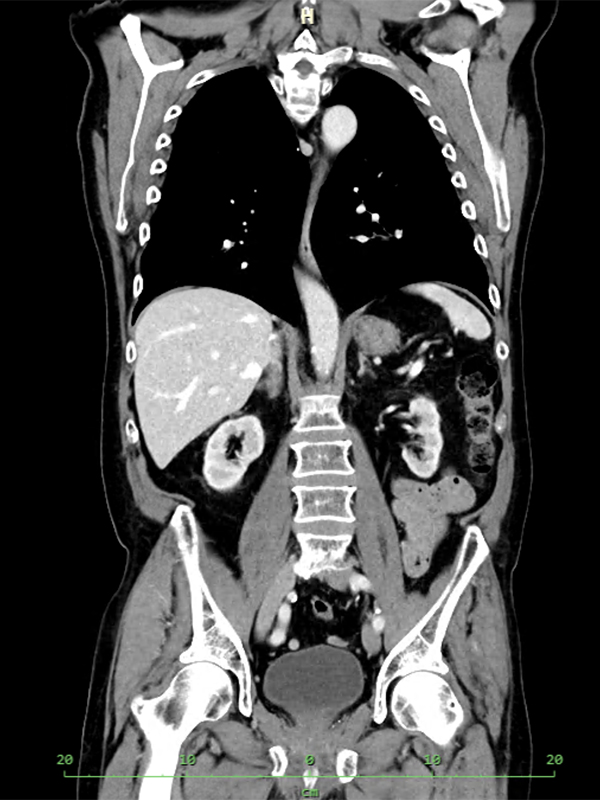

Počítačová tomografie (CT) bez kontrastní látky - k vyloučení/potvrzení močových kamenů

- pavilon B2 v 7:15 pokud lékař neurčí jinak

- datum a čas určí lékař

- lačnost

- žádanka vystavena elektronicky